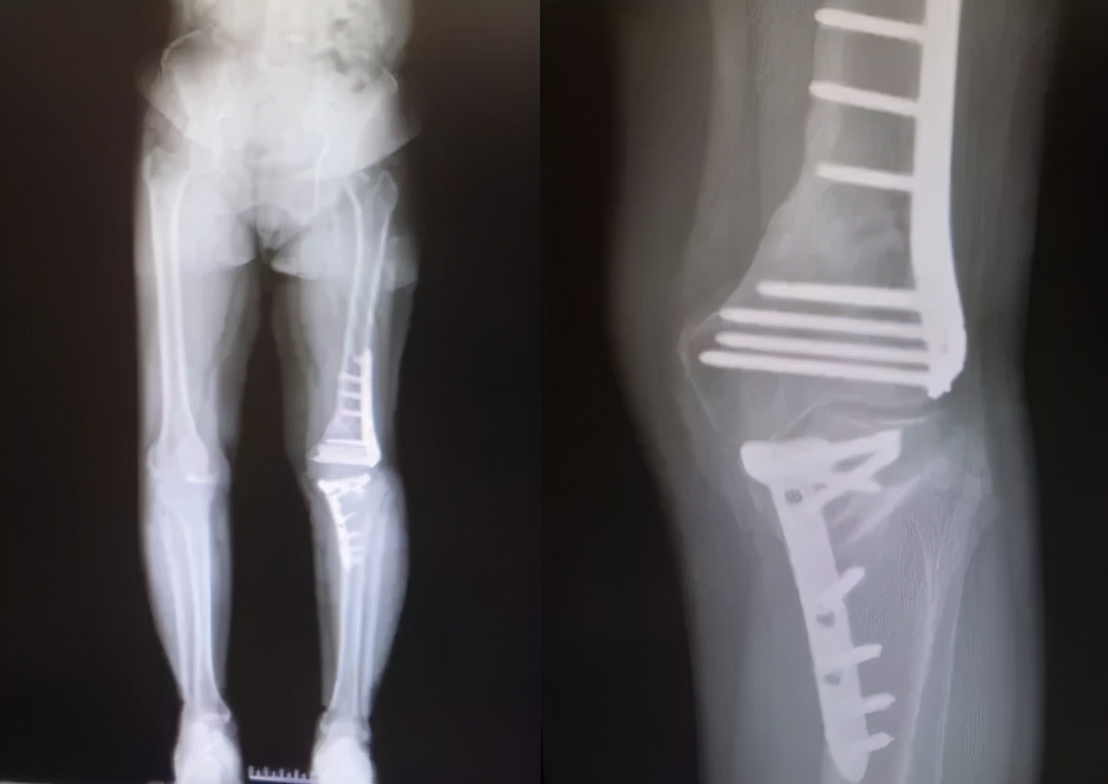

通过术前在计算机上精确规划截骨线及矫正角度后,刘万军主任团队对赵女士的左膝同时进行了股骨远端截骨术+胫骨高位截骨术。先取左膝关节的正中切口,行内松解后,按标准手术行髌骨修整。股骨切骨完整后,试装假体复位,调试后用骨水密固定安装假体。之后取左膝关节屈膝90度,采用外侧倒T行切口,分离胫骨外侧组织,在胫骨平台远侧2cm处截骨,用C形臂X线机检查位置,反复检查下肢对线,在腓骨前方行内固定。手术进行的非常顺利,出血少,历时约3小时10分钟。术后赵女士的膝关节疼痛消失,膝内翻畸形得到明显改善。

术后1年

刘万军主任介绍到,为了避免截骨术后关节线倾斜的发生,越来越多的学者主张在复杂畸形中应行股骨和胫骨的双部位截骨。股骨和胫骨双部位截骨的优势在于可以在维持关节线位置的同时,恢复膝关节正常解剖角度,从而保证下肢应力的合理分布。然而其也存在一些缺点,比如造成的创伤较大、术中发生并发症的可能性增加、康复及骨愈合的时间延长等。